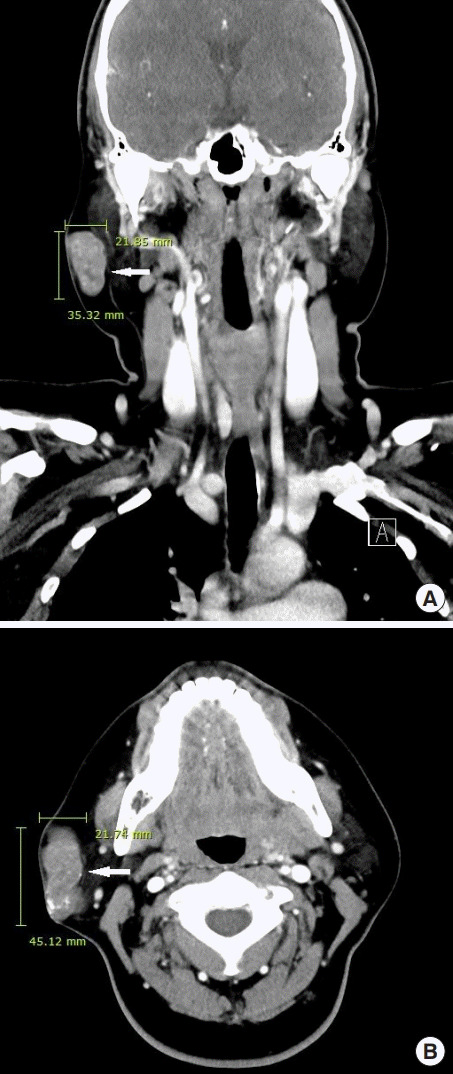

诊断时为35岁的张雨绮(女,化名)右侧腮腺区有肿块,就诊于佳学基因检测合作医院的整形外科。 肿块直径约 1 cm,张雨绮因无临床症状而拒绝手术切除。 然而,在怀孕的中晚期,肿块的大小增加到 5 厘米(图 1),并且变得疼痛。 分娩后肿块停止生长。 触诊肿块时,患者报告疼痛从腮腺区放射至耳后区。 病灶摸起来温暖、坚硬、淡蓝色和分叶状。 由于临床症状加重,患者同意接受手术切除肿块。

在本报告中,我们描述了一名 34 岁女性在右侧腮腺区域患有巨大毛母质瘤的病例。 最初发现肿块时,直径为 1 厘米,无症状。 然而,在患者怀孕期间,肿块长至 5 厘米并出现症状。 患者称,最初检测到肿块后右侧腮腺区域未发生外伤。